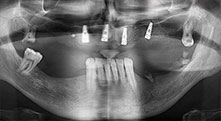

Bratu: Wir nutzen die Instrumente routinemäßig für die Entnahme von Knochenblöcken und das Spalten von Kieferkämmen. Weiterhin osteotomieren wir mit den Piezomed B6/B7 retinierte Zähne und entfernen nicht erhaltungsfähige Implantate. Alles Indikationen, bei denen es auf tiefe, saubere Schnitte ankommt.

Bratu: Wir bevorzugen Knochenentnahmen von der Linea obliqua externa des posterioren Unterkiefers, nicht aus der interforaminalen Region. Nach der Weichgewebsinzision verwenden wir die neuen Sägen, um den Umfang der Knochenentnahme zu definieren. Wir erledigen damit in fast 80 Prozent der Fälle auch die gesamte Präparation. Zusätzlich verwenden wir eventuell andere Piezo-Instrumente und zuletzt einen Meißel, um den Block zu mobilisieren. Das ist für uns eine sehr effektive Operationstechnik.

Bratu: Wir augmentieren im seitlichen Unterkiefer gern mit der Sandwich-Technik. Dabei wird ein Knochendeckel mit der Piezosäge präpariert und das krestale Fragment mit Mikroschrauben fixiert. Dazwischen platzieren wir eine Mischung aus autologem Knochen und xenogenem Knochenersatzmaterial. Das funktioniert sehr zuverlässig. Bei Kieferkammspaltungen im Unterkiefer sollten Sie nie auf ausreichend dimensionierte vertikale Schnitte verzichten. Sonst kann der Knochen leicht frakturieren.

Bratu: Ich halte Piezo für einen großen Sprung nach vorn für die Oralchirurgie. Die Technik macht Knochenpräparationen sicherer und leichter. Man verliert wenig Knochen, zum Beispiel bei Extraktionen. In der ästhetischen Zone ist dies sehr wichtig, vor allem wenn eine Sofortimplantation geplant ist. Auch für Weichgewebe ist Piezochirurgie ein Sicherheitsgewinn: Membranverletzungen in der Kieferhöhle sind im Prinzip Geschichte, ebenso Nervverletzungen bei Knochenblockentnahmen. Es gibt auch Daten, die geringere postoperative Schwellung und Beschwerden zeigen. Übrigens lassen sich mit Piezochirurgie auch sehr gut Kieferhöhlensepten präparieren. Nicht zuletzt profitieren unsere Patienten von der schonenden Arbeitsweise dieser Technik.